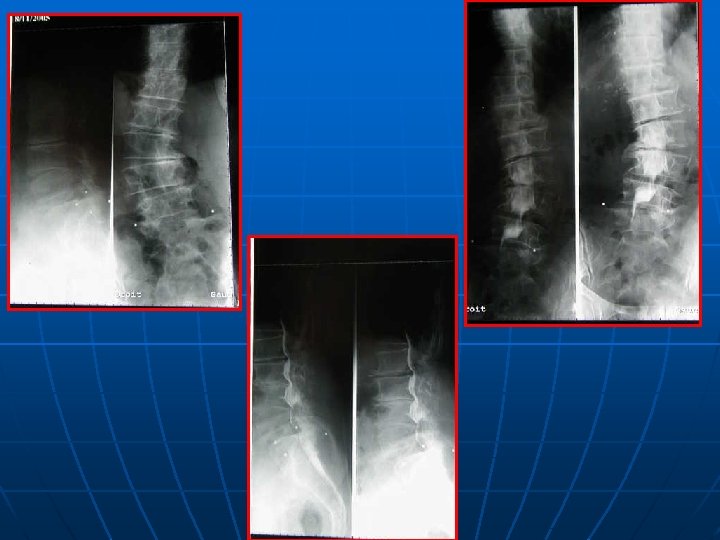

BILAN RADIOLOGIQUE STANDARD +++ n n TECHNIQUE : F/P debout incluant les têtes fémorales+++ STATIQUE RACHIDIENNE : *Face : rachis aligné ou inflexion voire rotation vertébrale scoliose angle COBB, analyser la hanche: coxarthrose!

BILAN RADIOLOGIQUE STANDARD +++ *PROFIL : +++ plusieurs paramètres - LL = S 1(L 5)-L 1 ou la vertèbre la plus inclinée! Moy : 60°-64°(L 5 - S 1 : 60 % LL) - IP (incidence pelvienne) = paramètre fixe Angle : milieu tête fémorale- ½ plateau S 1 - perpendiculaire au plateau de S 1 moyenne 50° - P. S. (pente sacrée)= 31 -42° - VP(version pelvienne)=12° IP = PS +VP PS/LL IP/PS

BILAN RADIOLOGIQUE STANDARD +++ n n SIGNES INDIRECTS DE CLE: *sagittalisation de l’IA *hypertrophie des articulaires *pédicules courts Spondylolesthésis dégénératif sagittal et frontal Visée pédiculaire: taille du pédicule+point d’entée CLICHES DYNAMIQUES INDISPENSABLES : Instabilité surtout en flexion

CLICHES GRAND FORMAT n INDICATIONS : * déséquilibre clinique frontal ou sagittal * scoliose et/ou modification de la courbure lombaire sur le profil ( LL, cyphose) * pas de corrélation entre l’IP et les autres paramètres pelviens * technique : debout, bras en légère antépulsion, base de crâne tête fémorale.

CLICHES GRAND FORMAT n RESULTATS – PARAMETRES : * Face : C 7 ou T 1 ½ sacrum déséquilibre D ou G * Profil : ° équilibre si C 7 derrière disque L 5 -S 1 derrière têtes fémorales+++ ° déséquilibre positif ou négatif ° IP, PS, VP, LL, CT